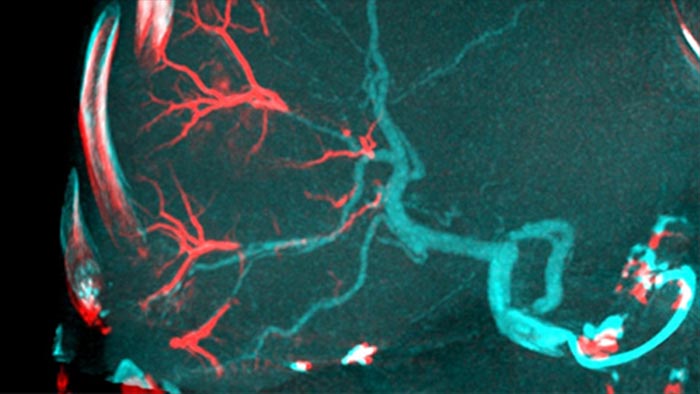

En ouvrant l’arc à gauche du patient, CBCT Open permet un positionnement décentré de la table du patient et ainsi un meilleur centrage du champ d’acquisition3-4. Il augmente de manière significative la couverture de l’image pour aider à visualiser les tumeurs à la périphérie du foie.4